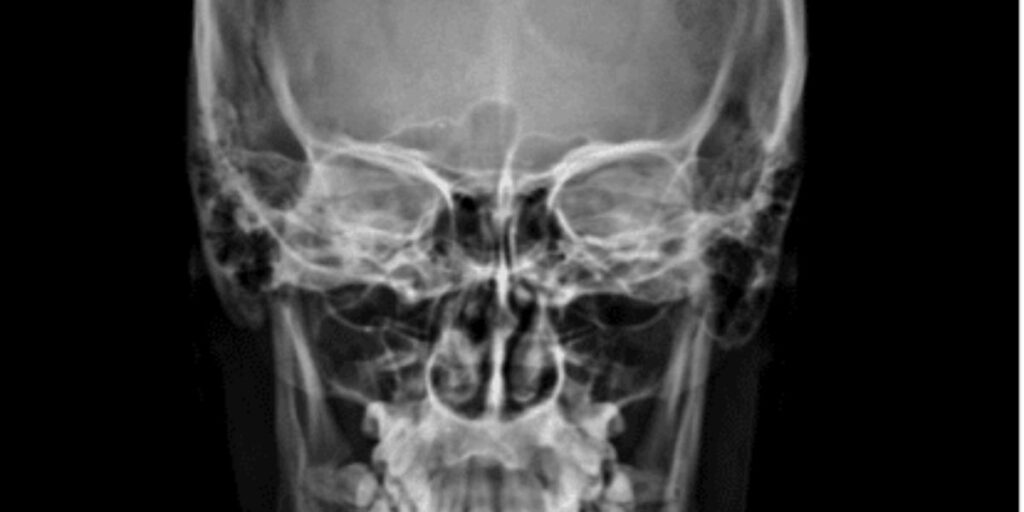

L’RX Orbite è un esame radiologico non invasivo che permette di acquisire immagini dettagliate delle orbite oculari. Il paziente viene posizionato davanti a una macchina a raggi X e, grazie a questa tecnologia, si ottiene una visualizzazione chiara delle strutture interne. Le immagini mostrano non solo le ossa, ma anche i muscoli oculari e i tessuti molli circostanti, consentendo ai medici del Poliambulatorio S-Medical Group di Sora di valutare con precisione ogni potenziale anomalia.

Durante l’esame di RX Orbite, il paziente viene esposto a una dose molto bassa di radiazioni ionizzanti. Le radiazioni attraversano i tessuti e le ossa dell’orbita, generando un’immagine radiografica precisa che permette di distinguere le diverse strutture. I tessuti più densi, come le ossa, appaiono più chiari, mentre i tessuti molli risultano più scuri. Questo contrasto consente ai medici di individuare eventuali anomalie con grande accuratezza.

L’RX Orbite permette di osservare le ossa che costituiscono le pareti dell’orbita (mediale, laterale, superiore e inferiore), la posizione del bulbo oculare, i muscoli oculari, i nervi ottici e le strutture vascolari. Queste informazioni dettagliate sono fondamentali per identificare fratture, alterazioni strutturali o anomalie nella posizione degli occhi.